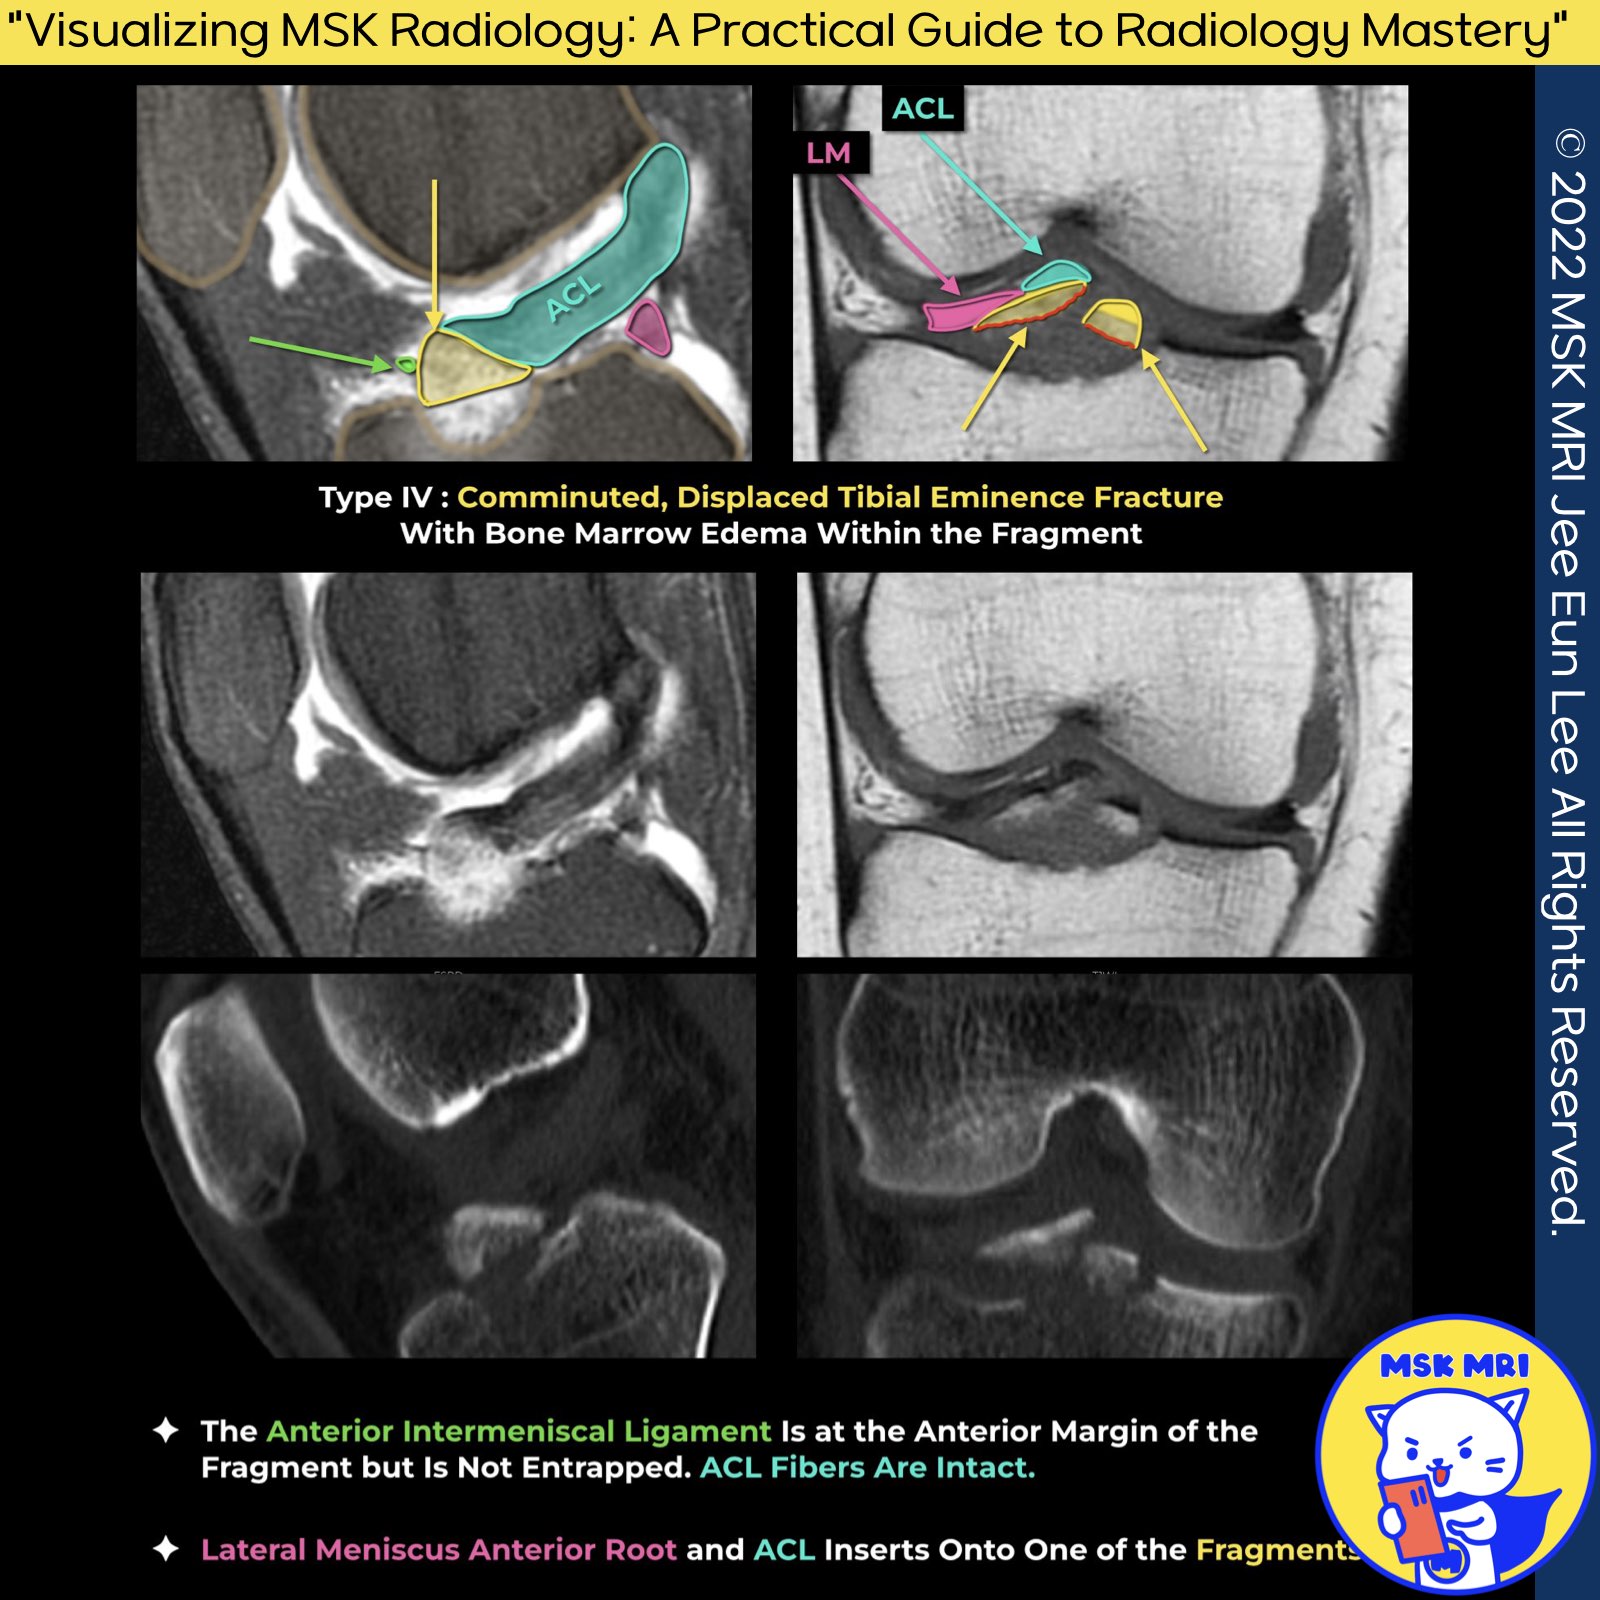

Type 4: Comminuted Avulsion Or Rotation Of The Fracture Fragment

1. Lateral Meniscus and ACL Attachments:

The study highlights a significant overlap (approximately 40%) between the anterior root of the lateral meniscus and the ACL's tibial attachment, observed under an electron microscope.

Notably, avulsed fracture fragments adhered to the anterior horn of the lateral meniscus.

2. CT Scans versus FSPD in Bone Fragment Visibility:

CT scans are superior in visualizing bone fragments compared to FSPD, mainly due to the clarity provided by bone marrow edema, surrounding fluid, and hemorrhage.